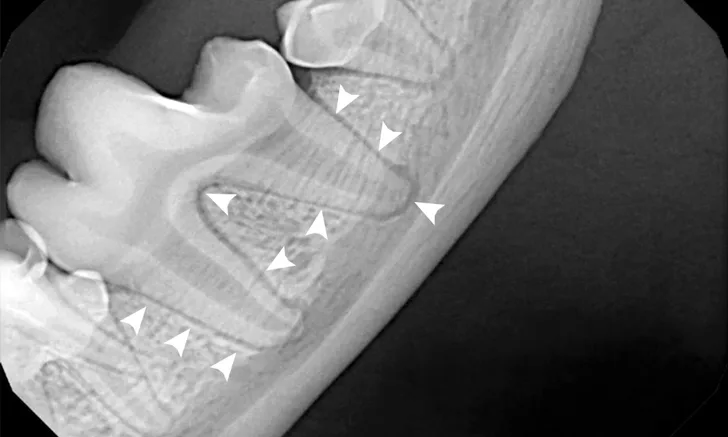

Dental radiography is useful when evaluating for periodontal disease. Use this image gallery to review essential findings in dental radiographs.

Interpreting dental radiographs can be tricky. Use this image gallery to review common abnormalities found on dental radiographs.